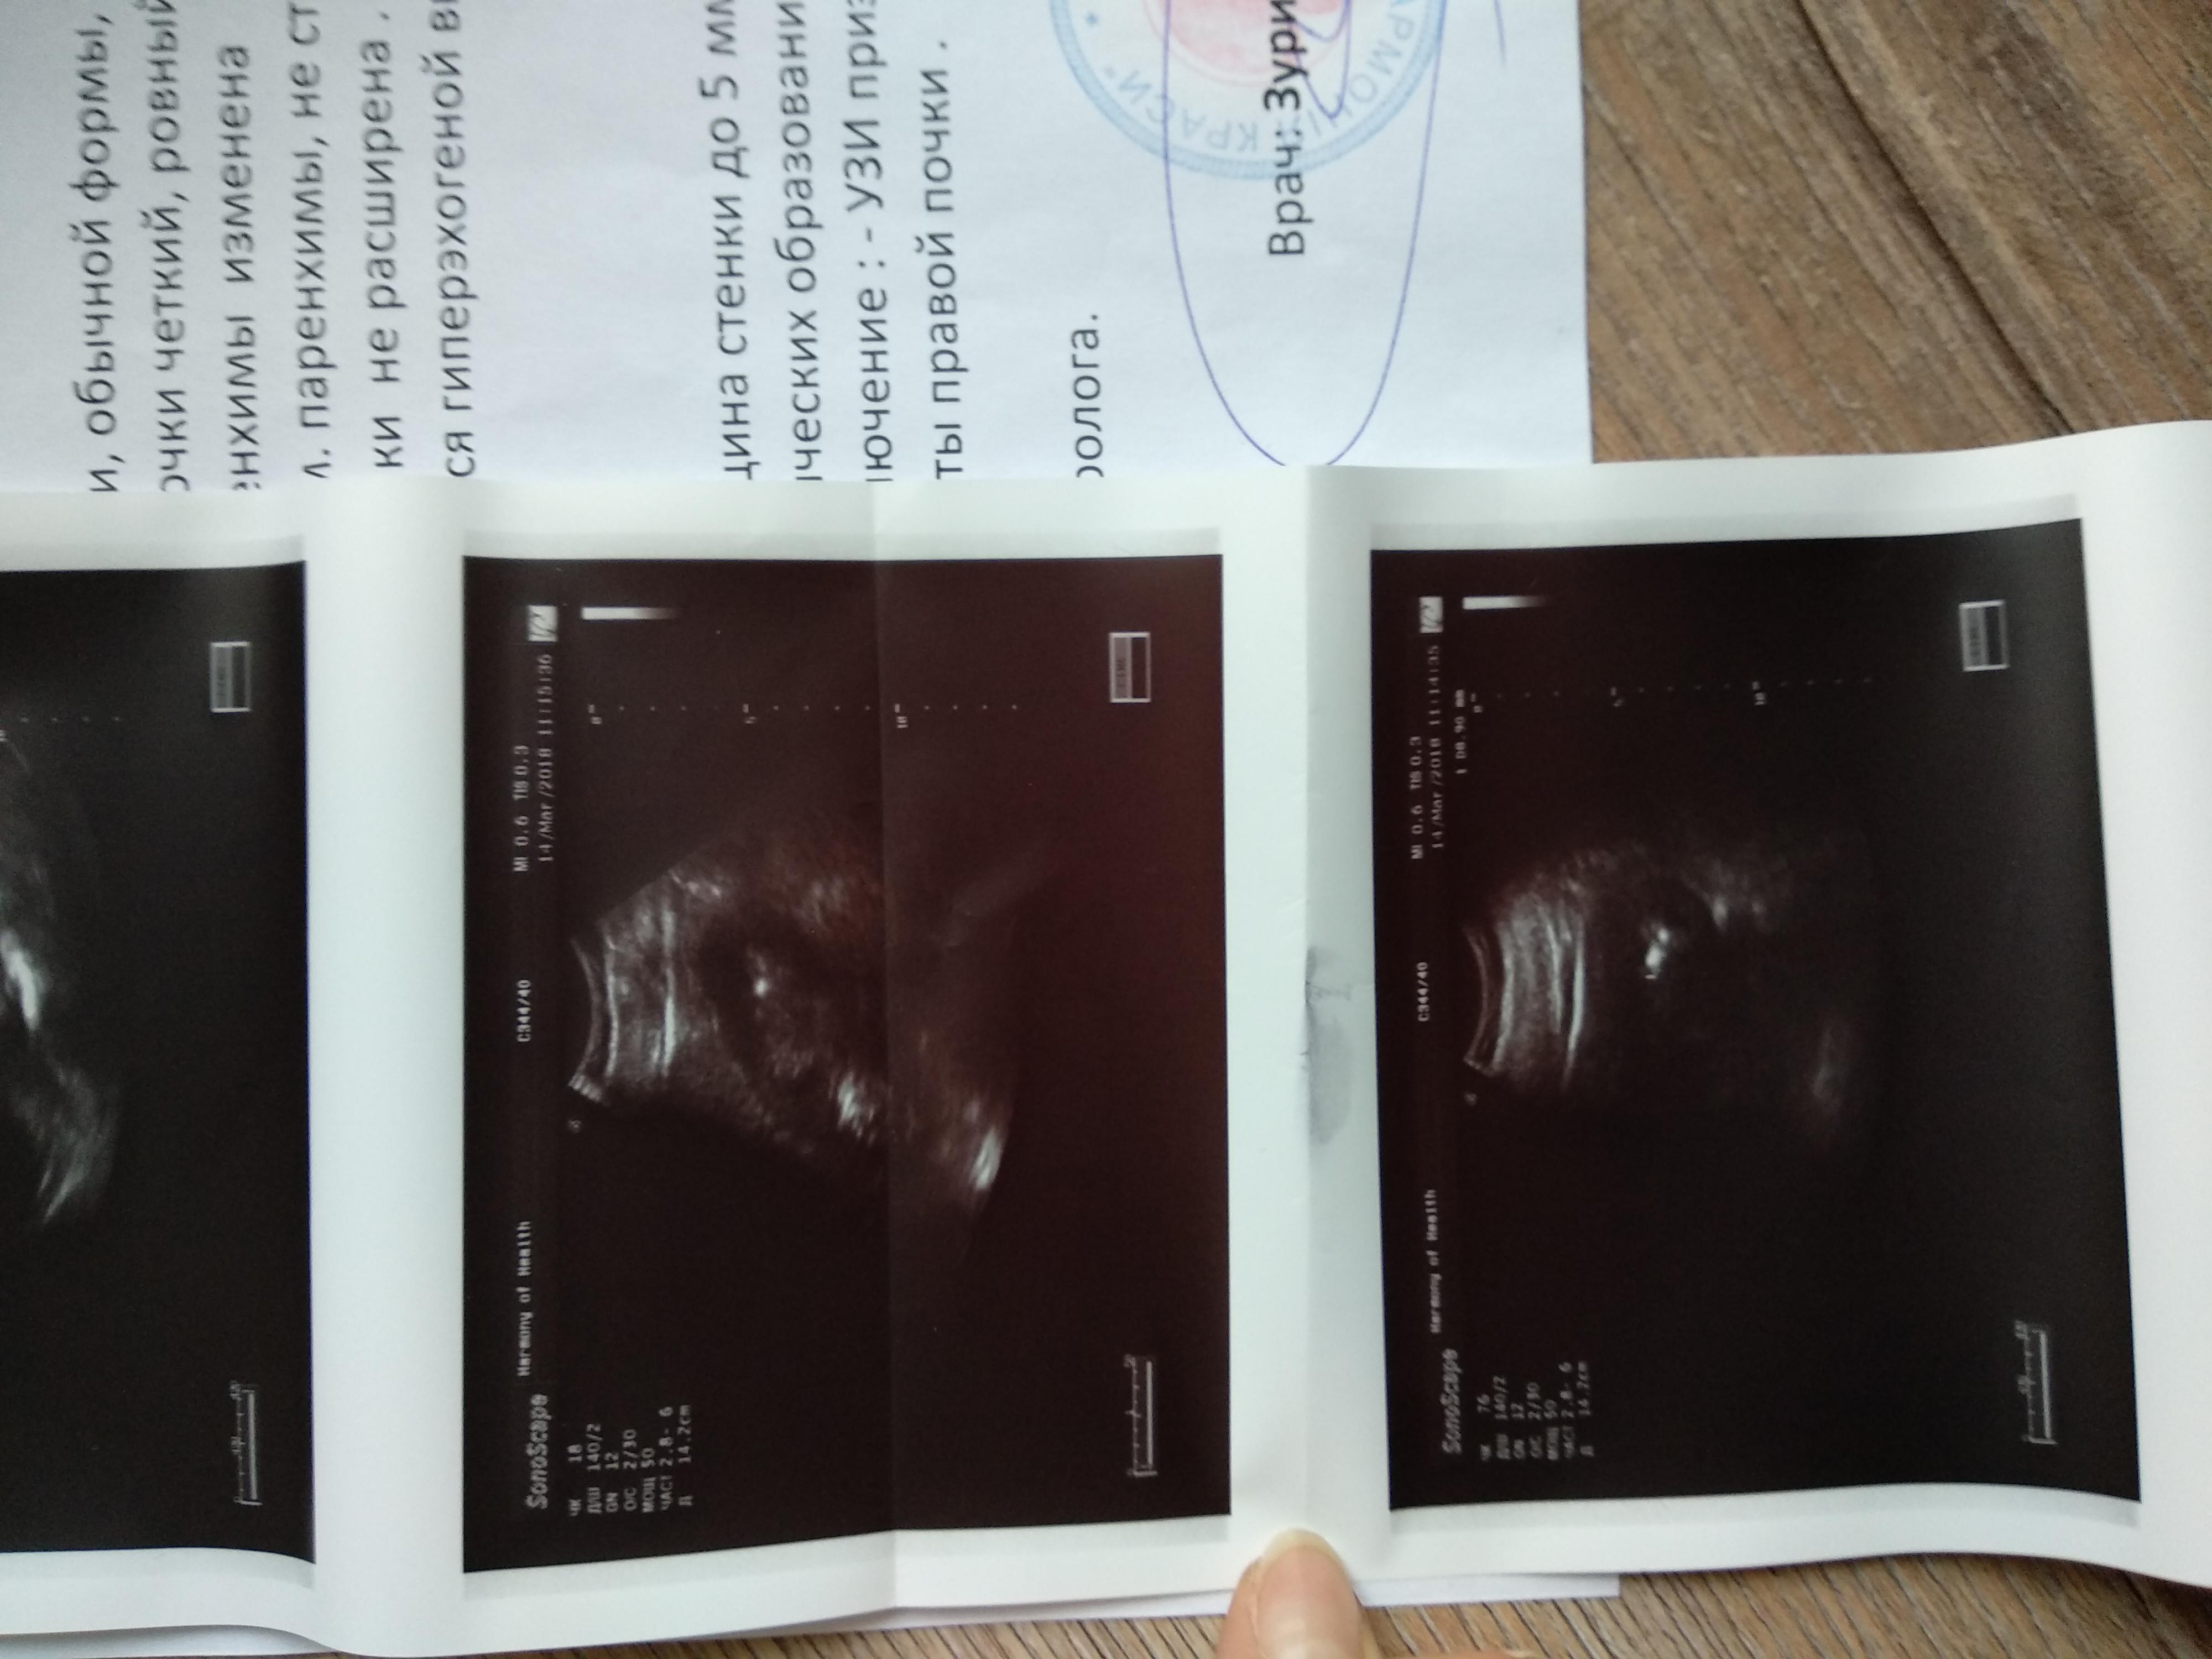

Мучают боли в почках, год назад сделали операцию пиелолитемию слева.

Необходимо дополнительное обследование для уточнения причин возникновения рецидива МКБ и выбора тактики ведения. Но для этого представленных Вами данным не достаточно, чтобы принять решение. Ваш вопрос требует изучения всех имеющихся у Вас медицинских данных. Мы готовы Вам помочь в принятии правильного решения, получения второго мнения на базе . Технически это можно сделать на нашем консультативном портале http://nethealth.ru/. Зарегистрируйтесь на нем, задайте вопрос мне, прикрепите сканы всех документов, которые у Вас имеются.